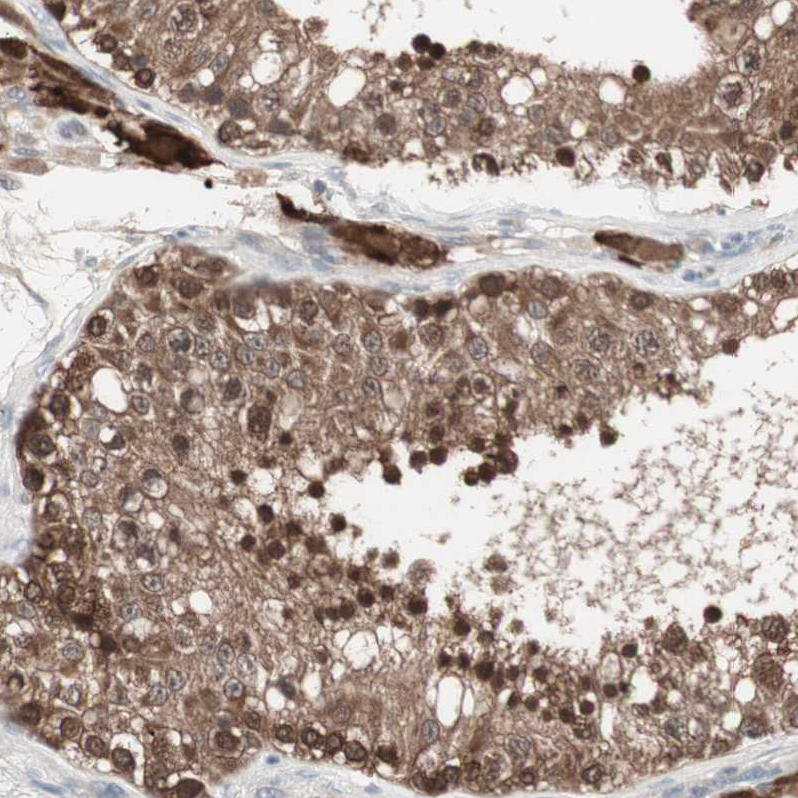

Immunohistochemical staining of human testis shows strong cytoplasmic and nuclear positivity in cells in seminiferous ducts and leydig cells.